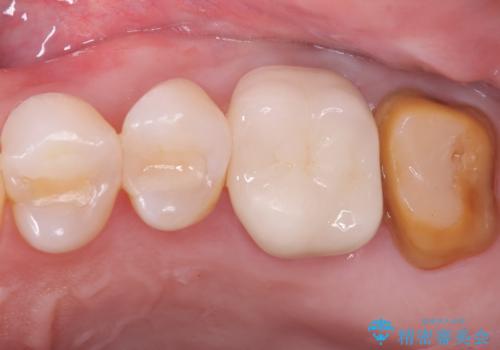

保険適応のメタルインレーと歯質との間に不適合な箇所を認め、補綴物のやり替えでの治療となりました。インレーからクラウンへ補綴物の形態を変更し、素材は清掃性・適合性・審美性の点からセラミッククラウンでのやり替となりました。

健全歯質の残存量から、クラウンでのやり替えを提案しオールセラミッククラウン(スタンダード)でのやり替えとなりました。

・オールセラミッククラウン(スタンダード) 121,000円(税込み)

・仮歯 11,000円(税込み)